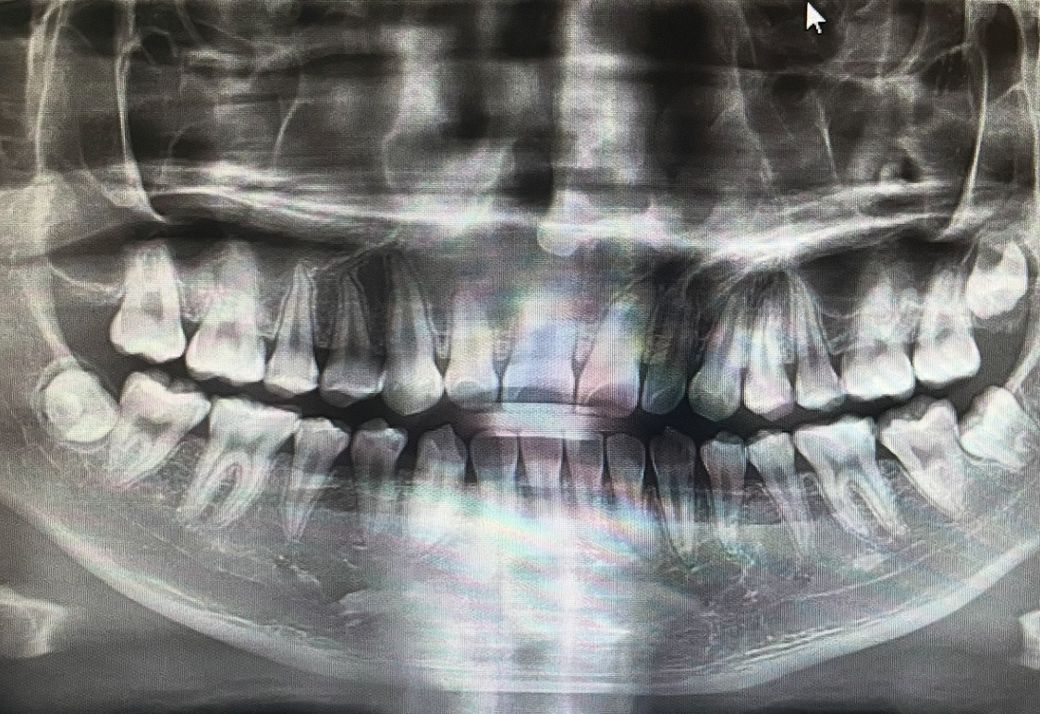

치과 엑스레이를 찍었는데요, 신경치료를 해야할까요?

제가 다른 치아에 충치가 생겨서 치과가서 치료하려 했습니다 엑스레이를 찍었는데 충치가 많다고 합니다 그중에서 심한게 있다던데 신경치료를 해야할수도 있다고 하더라고요… 이빨을 갈아봐야 알수 있다던데 엑스레이랑 이빨 사진(화질이 안좋습니다) 보면 신경치료 해야될까요?

엑스레이 상으로는 충치가 신경까지 진행된거 같지 않지만, 실제로는 충치가 깊어서 신경치료 가능성이 있어 보이긴합니다.

치아 직접 찍은 사진은 화질이 안 좋아서 잘 보이지가 않네요 다만 잘 찍어도 육안으로 보이는 충치가 신경치료가 필요한 정도일지는 판단하지 못합니다.

신경치료는 증상이 명확하면 하는 것이 좋습니다. 엑스레이상에서도 신경치료를 지금 당장 해야한다는 소견이 나오는 치아는 없습니다

방사선 사진이나 찍어 놓은 사진으로는 신경치료의 여부를 정확하게 확인하기 어려워 보입니다. 충치가 범위가 넓어서 신경까지 진행되어 있다면 신경치료가 필요할 수 있습니다

자세한 확인을 위해서 치과에서 진료를 받아보는 것을 권유드립니다.